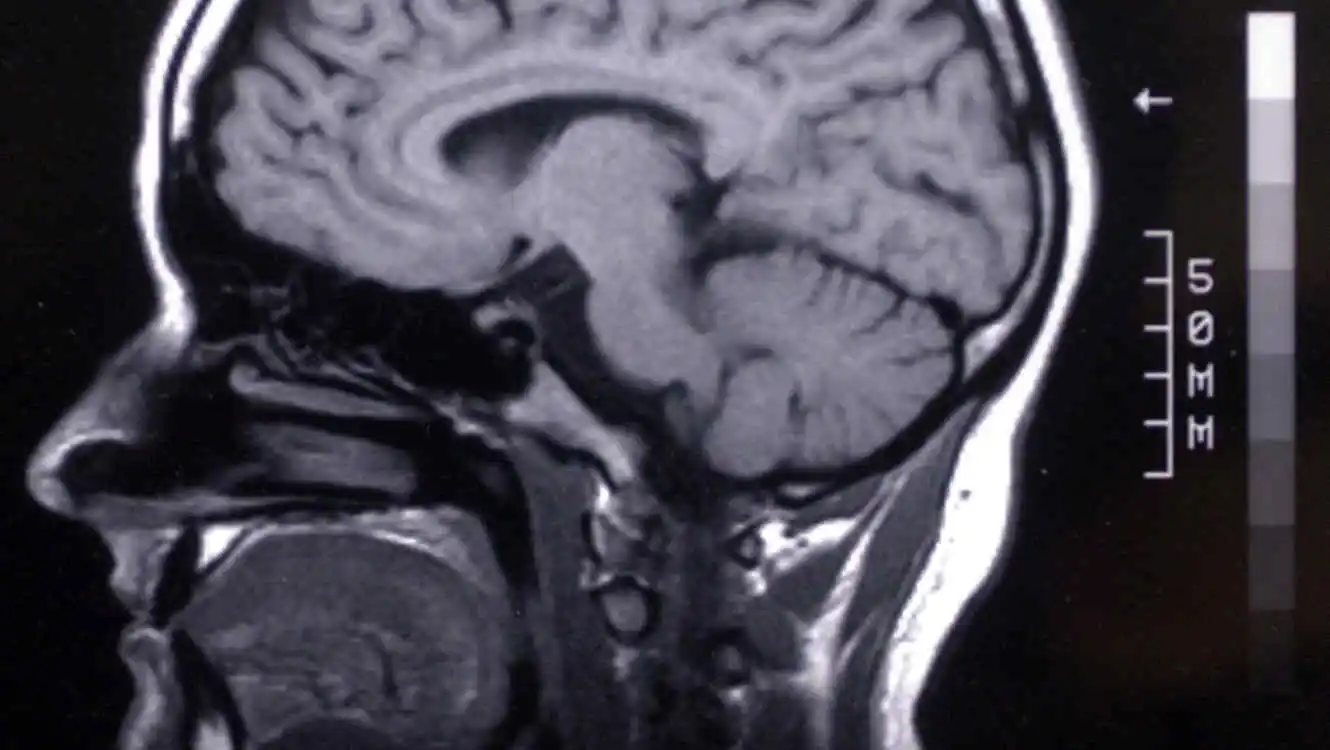

Científicos descubren dos ‘recetas’ para frenar el envejecimiento del cerebro